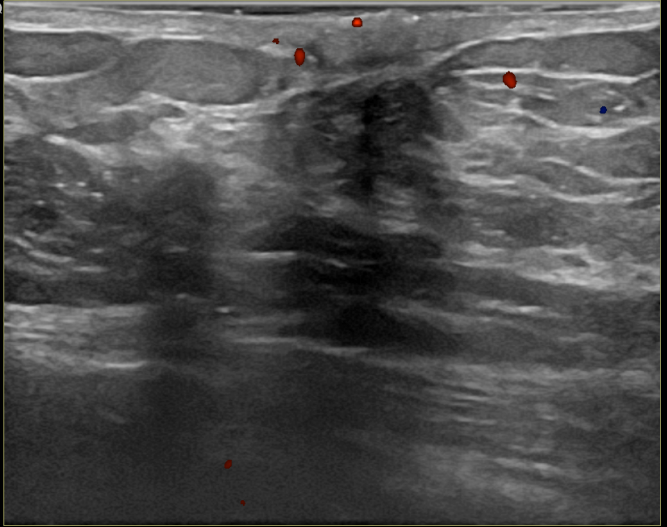

상기환자는 외부검사이상으로 조직검사위해 내원하신 60대초반 여성분으로 의심스러운 좌측혹 조직검사 시행해 침윤성암으로 진단되었습니다